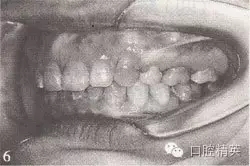

参见图9-33 双侧后牙锁颌矫治前后

B.双侧后牙锁颌矫治后